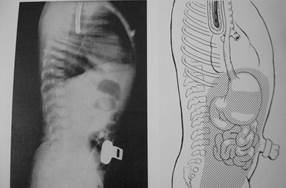

Рис.16. Рентгенологическое исследование при левосторонней ложной диафрагмальной грыже (боковая проекция).

Рис.17. Рентгенологическое исследование при левосторонней ложной диафрагмальной грыже (прямая проекция).